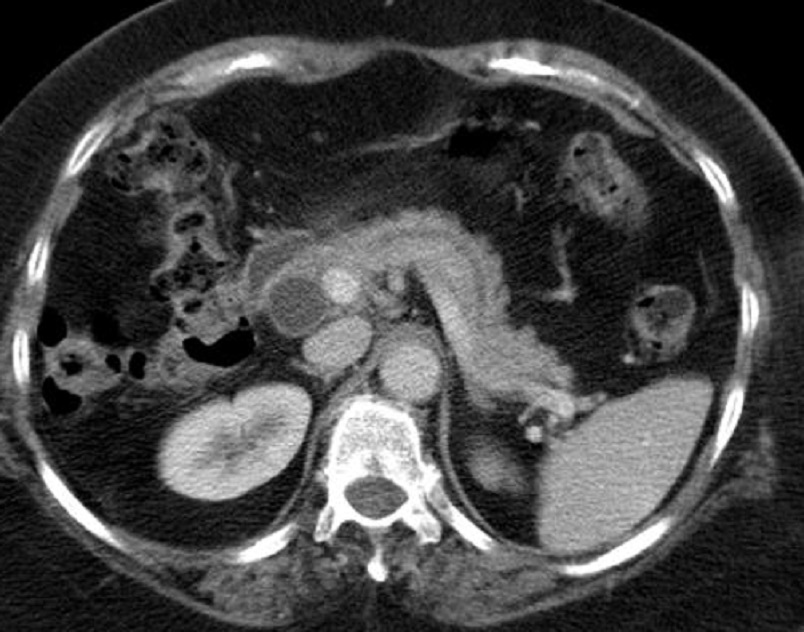

Image

radiologique TDM d'une adenocarcinoma de la tete du

pancreas en coupe axiale . Aspect lesionnel est un

masse hypodense a bord iregulier , l.a tete et le

corp du pancreas est deformation et tumefie .(

fleche rouge ) |

|

Parfois aspect lesionaire

est isodense ( fleche rouge ) . Par sa propiete de

moins de rehaussement de contrast intraveineuse

image radiologique du tumeur serait devenir nettete

sur les coupe TDM plus C+ . Image radiologique TDM

en coupe axiale ( n'a pas de contrast intraveineuse

) |